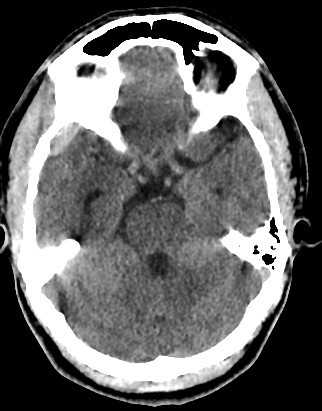

• 30 years old male with trauma

• A well-defined extraxial elliptical shape fresh blood density seen in the right fronto-parietal region.

• The lesion measured ……. cm in its maximal dimensions.

• The lesion exert little mass effect in the form of effacement of the cortical sulci and and mild midline shift.

• right fronto parietal subglial hematoma seen

• associated right fronto parital fracture seen

• no brain herniation.

• Normal size and configuration of the ventricular system.

• No intracerebral or intraventricular recent blood density.

• Normal appearance of the brain stem and cerebellum.

acute extradural hematoma with fracture